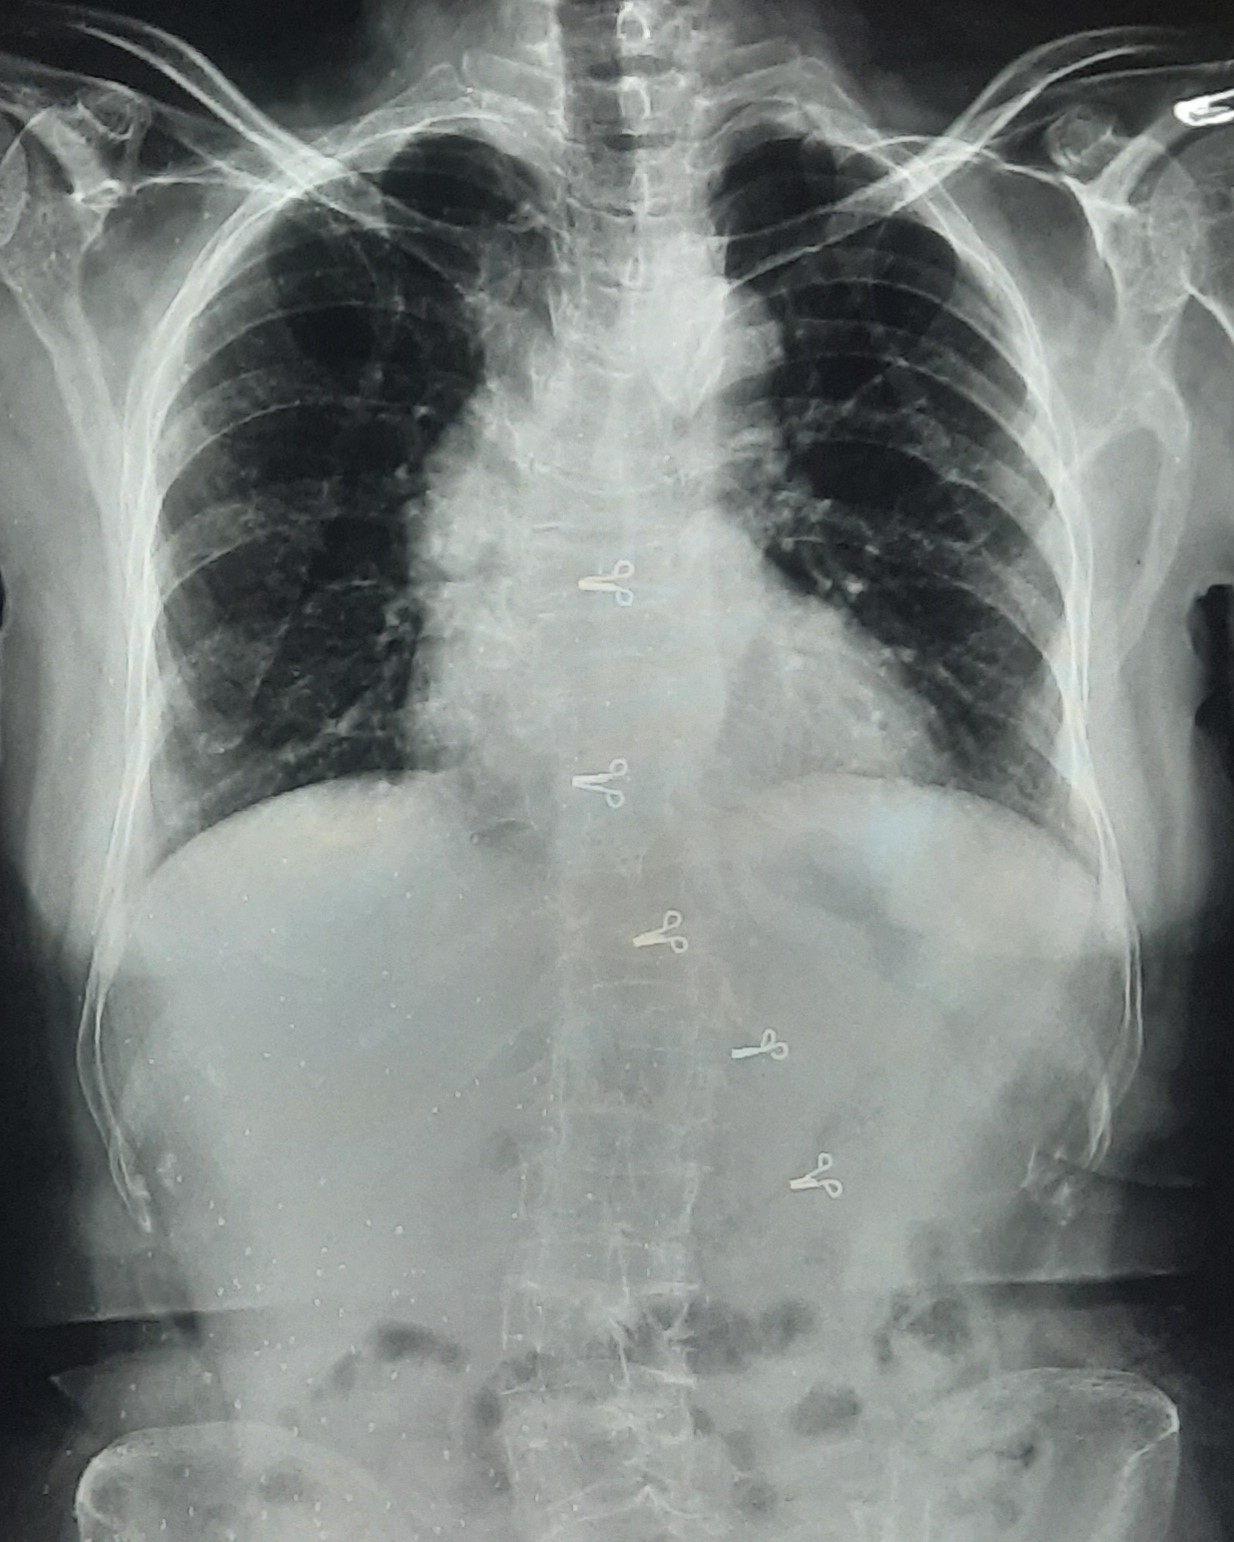

| 318 | IGGMC, Nagpur, Nagpur | P2 | 29-4154 | Tahera Bee | Consent taken on Paper | 70 Yrs. |

Provisional Diag : Post TB Bilateral Bronchiectasis

Final Diag : Post TB sequalae, Bilateral Bronchiectasis In Lower Lobe With Type 1 Respi Failure With Sepsis With Septic Shock With SYST HTN |

Post TB Sequelae | Abnormality visible on x-ray |